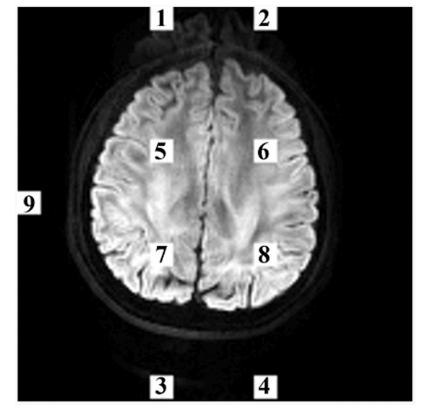

Fig. 7. Selected regions in ghost-to-signal ratio calculation. Each region has 9 ×9 voxels. Mean signal intensities in regions 1–4 are NIt, in regions 5–8 are SIt, and in region 9 is BI, where t = 1,2,3,4.

图7:在计算伪影与信号比率时所选的区域。每个区域有9×9个体素。区域1至4的平均信号强度为(NI_t),区域5至8的平均信号强度为(SI_t),区域9的平均信号强度为(BI),其中(t = 1,2,3,4)。